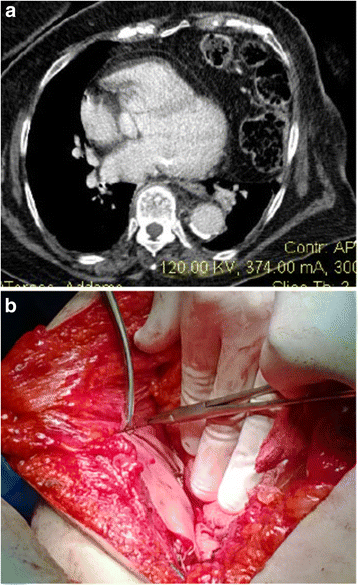

Case 4: A 63-year-old woman was admitted with complaints of breathlessness for 2 days, which was gradually progressive and associated with left-sided chest pain and a dry cough. There was a history of a vehicle accident 6 years ago. The initial chest radiograph revealed an elevated left hemi diaphragm with presence of a colon gas shadow in the lower half of the hemithorax. CT scan suggested left diaphragmatic hernia which allowed passage of the spleen, left lobe of liver and transverse colon (Fig. 4a). Surgery was performed in emergency, reducing contents and repairing the defect with biological mesh (Fig. 4b; Tutomesh, bovine pericardium mesh ®). The patient was discharged on the 10th post-operative day, without complications.